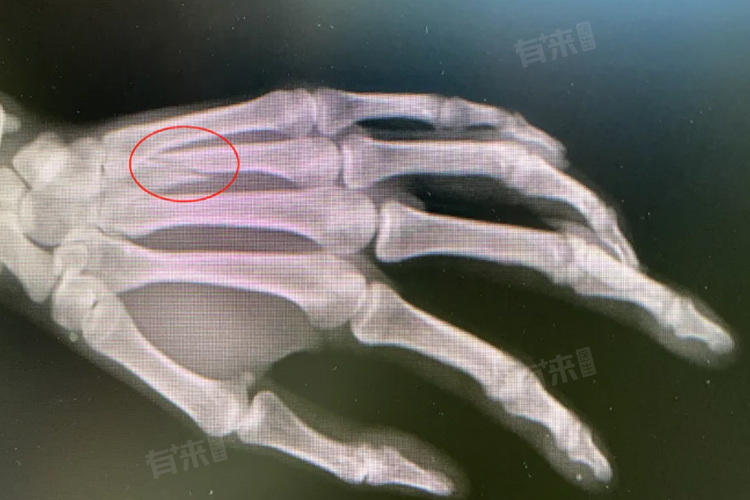

5、影像学检查:如果以上症状和体征均存在,及时就医并进行影像学检查,如X射线检查、CT扫描或断层扫描检查等。这些检查能够直观地显示骨骼的结构和损伤情况,对确诊骨裂具有重要意义。